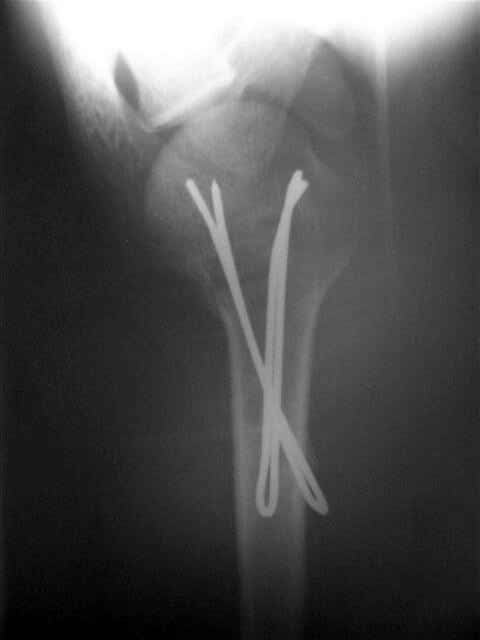

Re: Перелом шейки плеча

Спасибо за участие в дискуссии -перелом шейки плеча, для себя я прояснил многие технические моменты...

Посылаю послеоперационные Рг граммы.